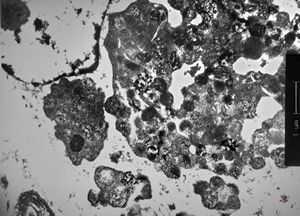

myelinoid inclusion

myelinoid inclusion in an unclassified tumor - peroxisome?

myelinoid inclusion in an unclassified tumor - peroxisomes?